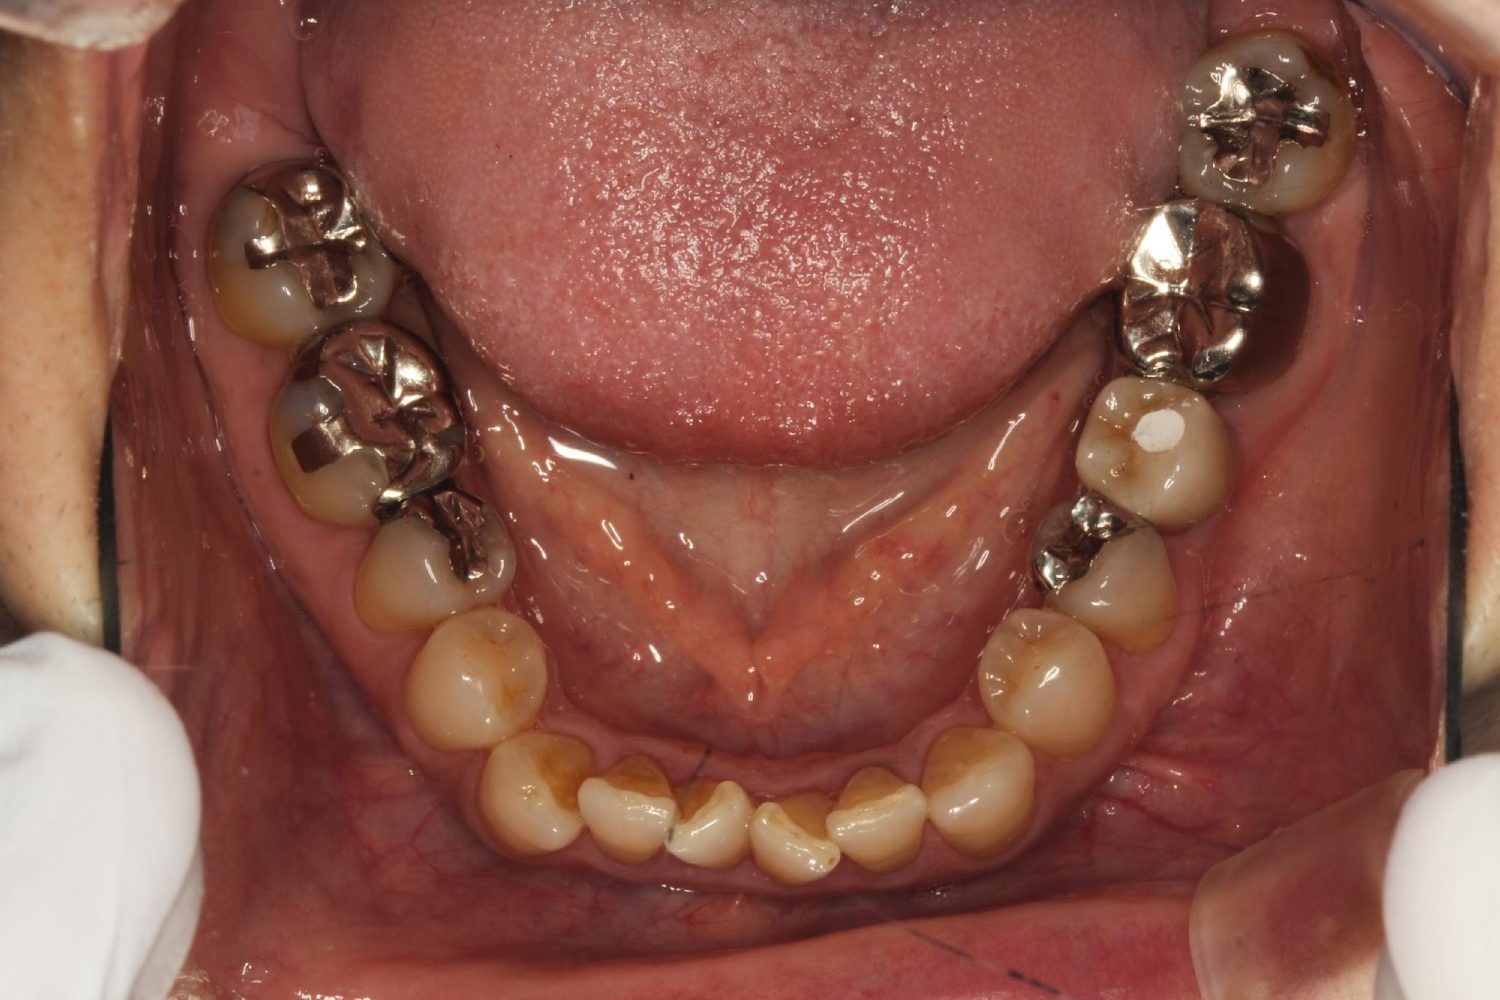

インプラント治療の症例紹介③

Before

After

主訴

むし歯の治療

治療内容

保存不可能な歯の抜歯

下顎にインプラント埋入し咬合再構成

治療費

2,688,400円(税込)

治療期間

14か月

治療回数

21回

想定されたリスク

※上部構造の形態が複雑になるため清掃が難しくなる。インプラント周囲炎の恐れがありました。

多数歯う蝕および多数歯欠損による咬合崩壊、保存不可能な歯の抜歯により上下無歯顎に。下顎に6本インプラント埋入する事で咬合再構成を行った。